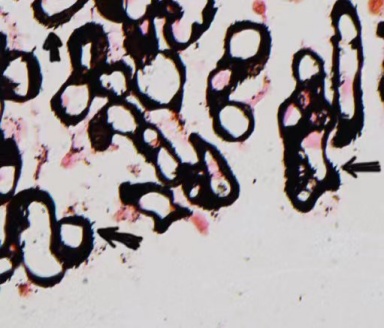

为了找到真凶,医生为老刘做了肾脏穿刺活检病理检查。病理结果是:膜性肾病。

真相终于大白: 是这个早期的肾脏肿瘤,刺激免疫系统产生了异常反应,免疫复合物像垃圾一样堵塞了他的肾小球,导致蛋白质大量漏出,最终表现为水肿和蛋白尿。外科医生为老刘试行了手术及后续治疗。手术后,老刘的蛋白尿和水肿也逐渐消失了。